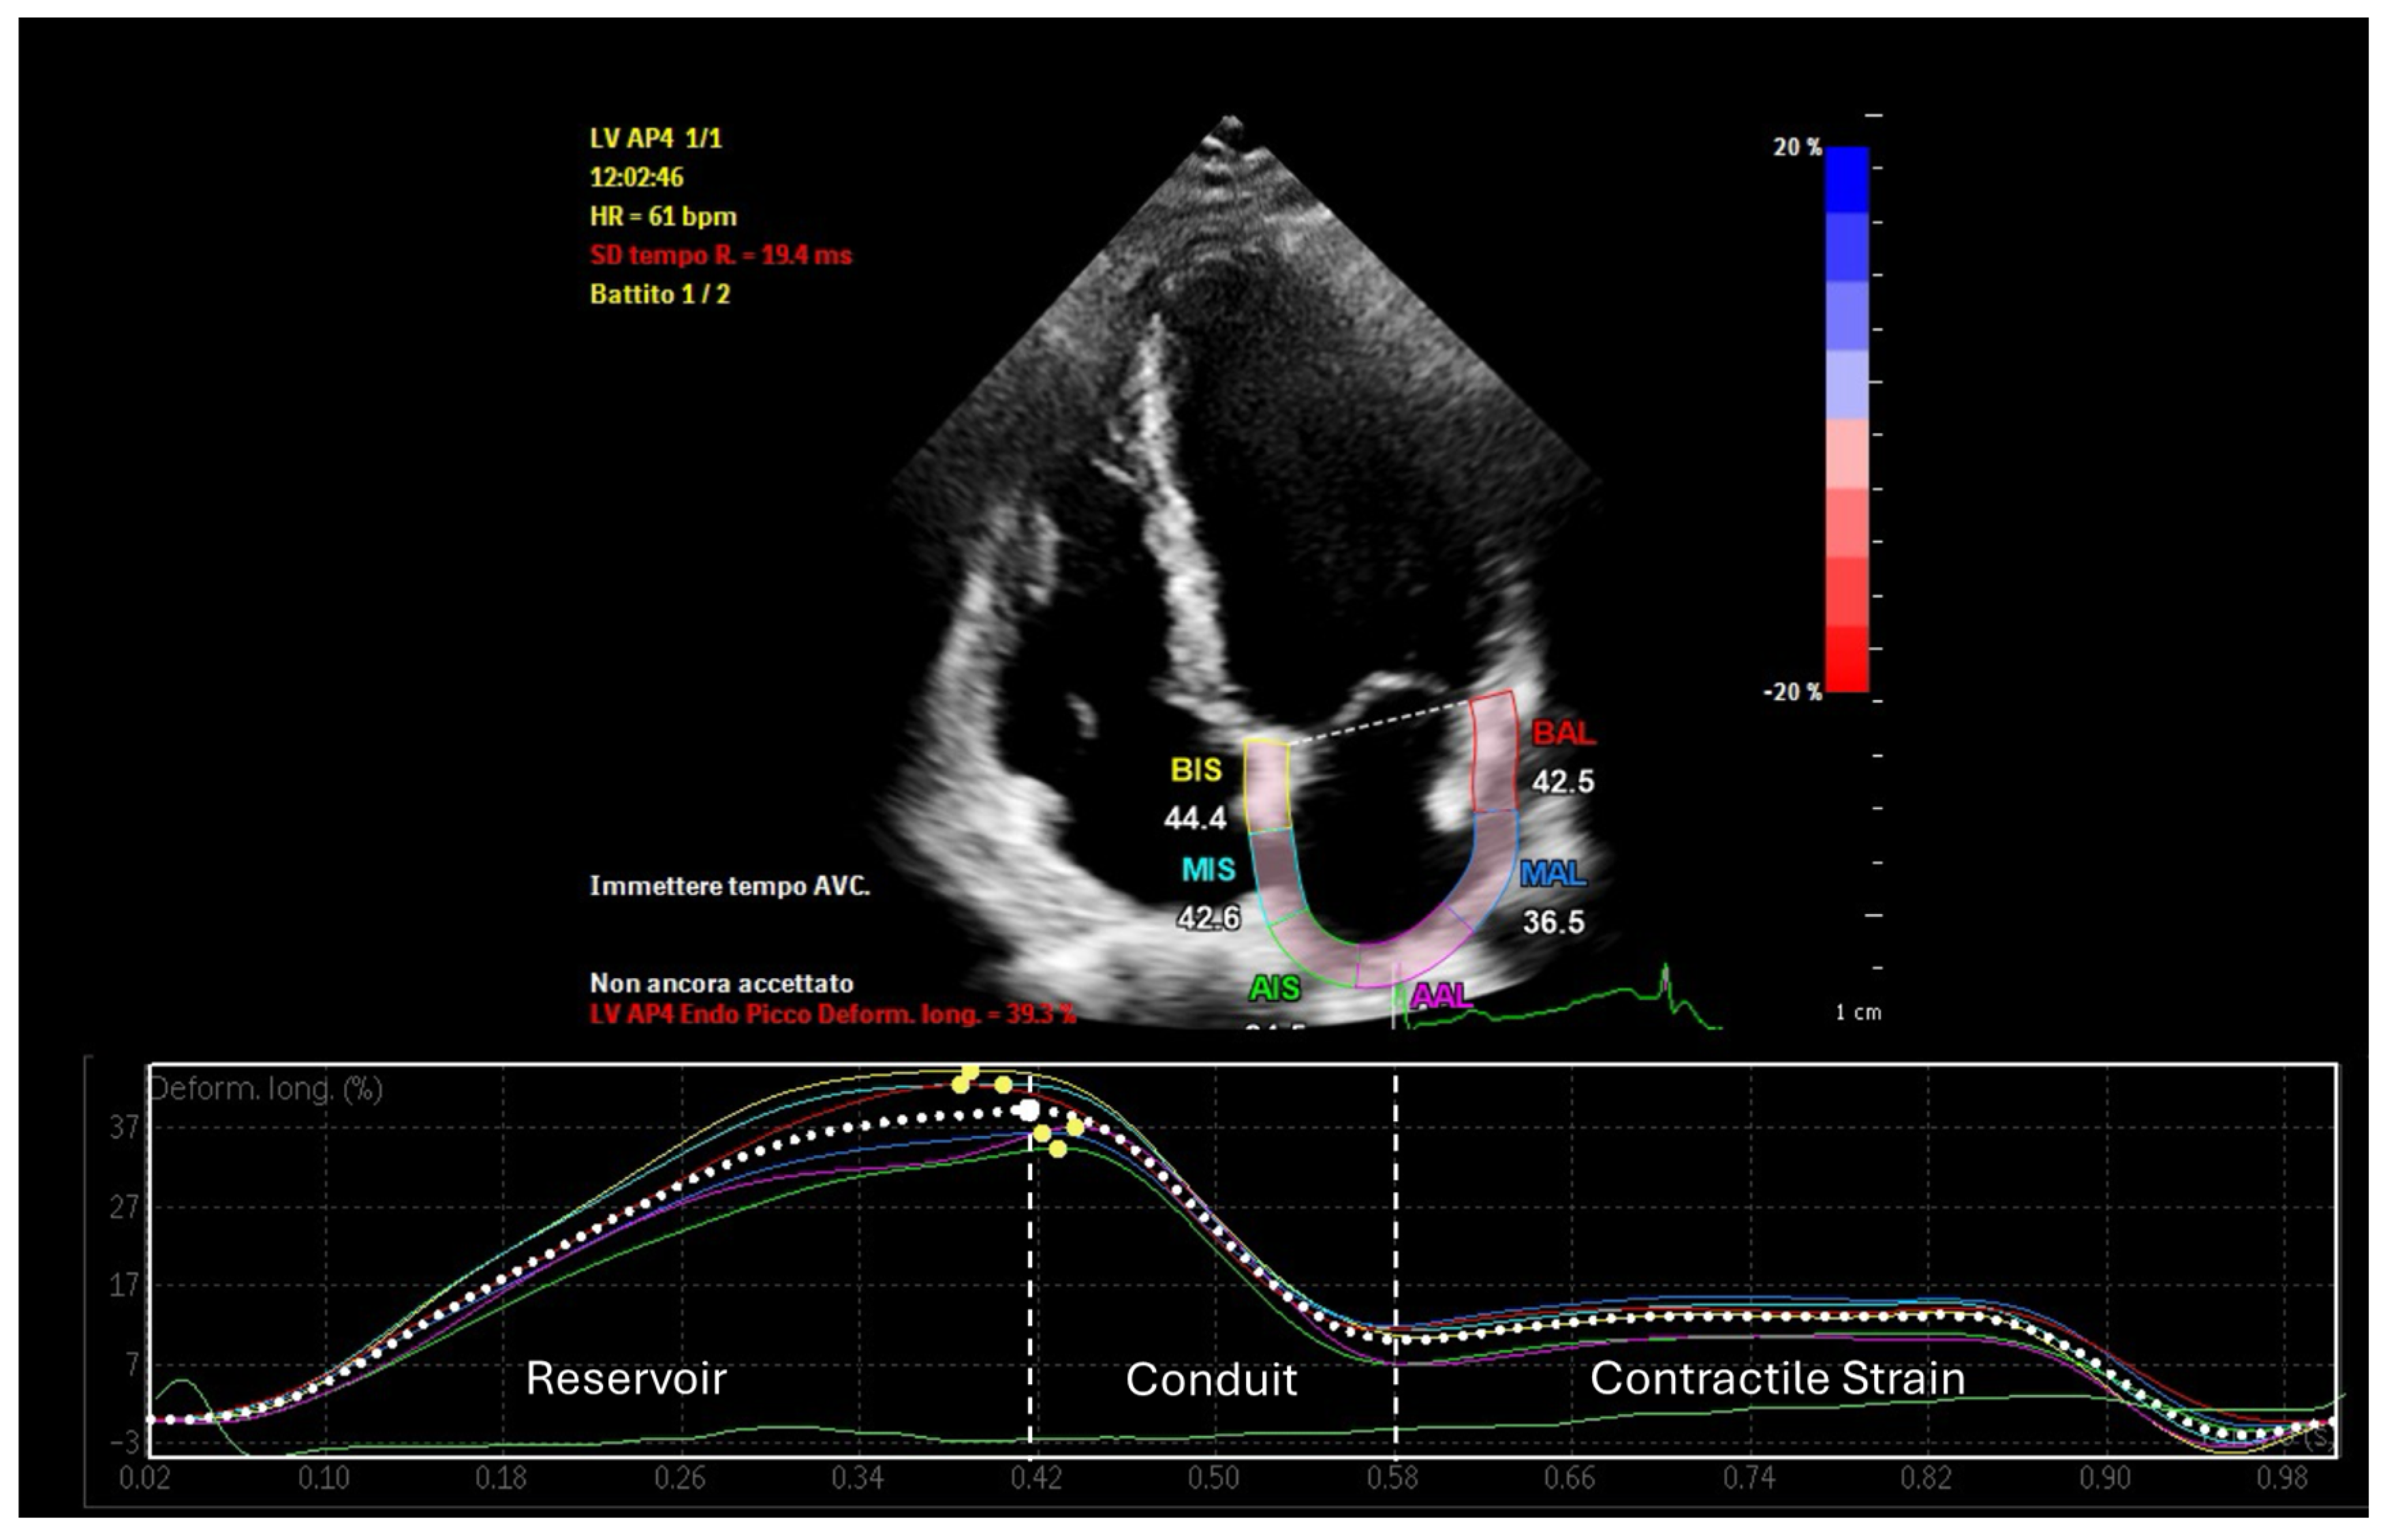

Left atrial strain, measured using speckle-tracking echocardiography, has emerged as a valuable tool for non-invasive assessment of atrial function. This technique evaluates myocardial deformation, dividing the imaging results into three phases: reservoir strain, conduit strain, and booster strain (Figure 1) [8]. Strain imaging enables early detection of atrial dysfunction before structural abnormalities become apparent, facilitating timely intervention and risk stratification [9]. This review examines the interplay between LA-EAT and atrial remodeling, emphasizing the clinical utility of atrial strain analysis in screening, management, and prognosis.

Figure 1.

Phases of left atrial strain in a healthy subject.

- Reservoir function (positive strain): Peak atrial longitudinal Strain (PALS) measures the atrial expansion during ventricular systole, when the atrium fills with blood from the pulmonary veins, reflecting atrial compliance and the ability to accommodate pulmonary venous return. Reduced reservoir strain is indicative of impaired atrial compliance, which can result from increased EAT-induced fibrosis or inflammation.

- Conduit function: This assesses the atrium’s role as a conduit during early ventricular diastole, reflecting its capacity to passively transfer blood from the pulmonary veins to the left ventricle. Decreased conduit strain suggests early atrial stiffening or impaired ventricular filling, conditions often exacerbated by EAT-related paracrine dysfunction.

- Contractile strain: Peak atrial contraction strain (PACS) measures the active contraction of the atrium during late diastole. A reduction in contractile strain points to impaired atrial contractility, potentially caused by the mechanical compression and electrical remodeling induced by LA-EAT.

In healthy subjects, typical values for left atrial reservoir strain range from 35 to 45%, conduit strain from 18 to 25%, and contractile strain from 10 to 15% [45]. In contrast, patients with increased LA-EAT often exhibit markedly reduced values (Table 2): reservoir strain below 25%, conduit strain reduced to 12–18%, and contractile strain falling below 8% [46]. These reductions reflect the adverse mechanical and inflammatory effects of LA-EAT on atrial function.